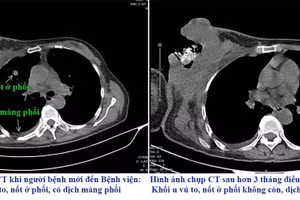

GD&TĐ - Dù đã trải qua 16 đợt hóa trị, bệnh nhân vẫn đáp ứng kém và gặp nhiều tác dụng phụ như viêm phổi, viêm dạ dày, rụng tóc, mệt mỏi kéo dài.